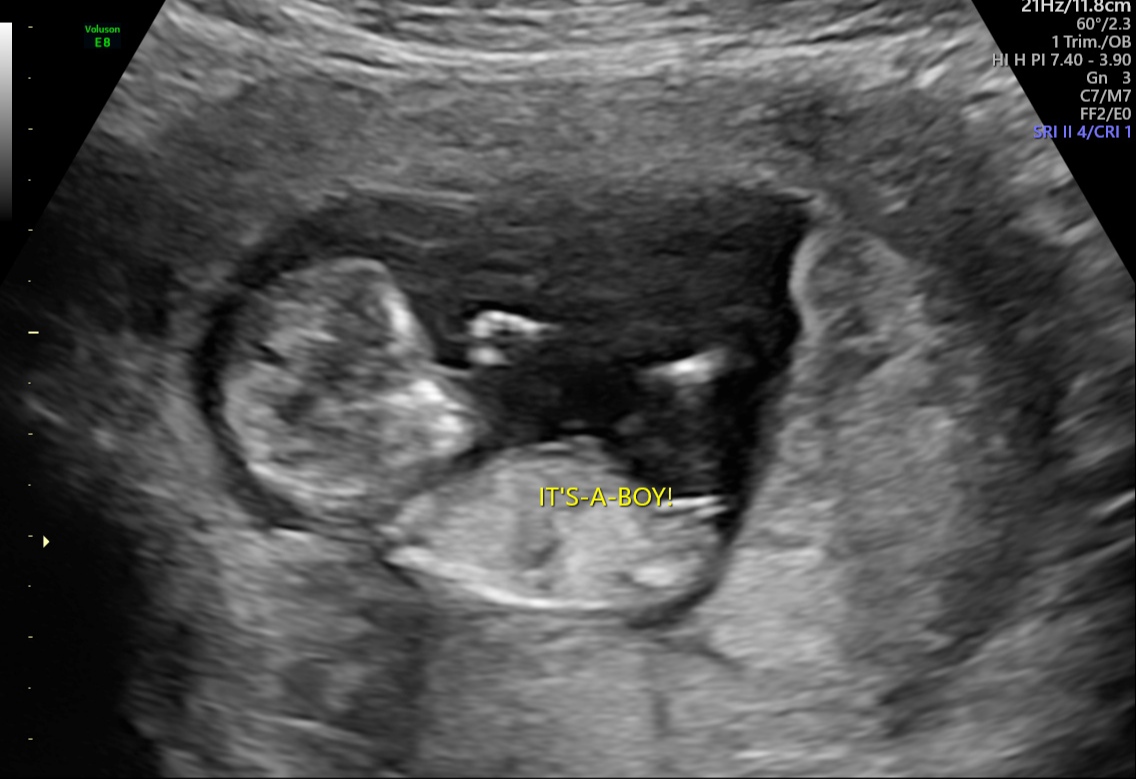

jsem v 12.tt a včera mi oznámili, že je to kluk, ale ja mám stále ten pocit, že je to holka. Každopádně hlavní je, aby bylo maličké zdravé.

Co myslíte? 😁 😊

z fotky, co jste přiložila, bych řekl, že naopak je to na 90 % holčička ! 🙂